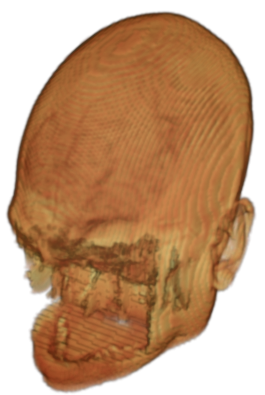

To prevent these types of attack, medical scans are currently de-identified using crude removal-based techniques [Bischoff-Grethe et al.(2007)Bischoff-Grethe, Ozyurt, Busa, Quinn, Fennema-Notestine, Clark, Morris, Bondi, Jernigan, Dale, Brown, and Fischl, Schimke et al.(2011)Schimke, Kuehler, and Hale, Milchenko and Marcus(2013)] which seek to remove privacy-sensitive parts of the head (examples in Figure 3). However, as we demonstrate, these existing techniques fail to reliably hide the patient’s identity – or they are so aggressive that they impair further medical analyses. A better solution is needed.

Benchmark De-Identification Methods. We compare our result with three publicly available and widely-established methods for de-identification of MRI head scans, depicted in Figure 3. All methods have in common that they (1) are not deep-learning-driven, (2) require no additional training and (3), are used on a day-to-day basis in neuroscience and clinical research. All procedures were applied with default settings on images of resolution . The methods include QUICKSHEAR [Schimke et al.(2011)Schimke, Kuehler, and Hale], FACE MASK [Milchenko and Marcus(2013)], and DEFACE [Bischoff-Grethe et al.(2007)Bischoff-Grethe, Ozyurt, Busa, Quinn, Fennema-Notestine, Clark, Morris, Bondi, Jernigan, Dale, Brown, and Fischl]. Descriptions of the methods are provided in the Appendix. We also include MRI WATERSHED [Ségonne et al.(2004)Ségonne, Dale, Busa, Glessner, Salat, Hahn, and Fischl], a skull-stripping method that removes everything except the brain.